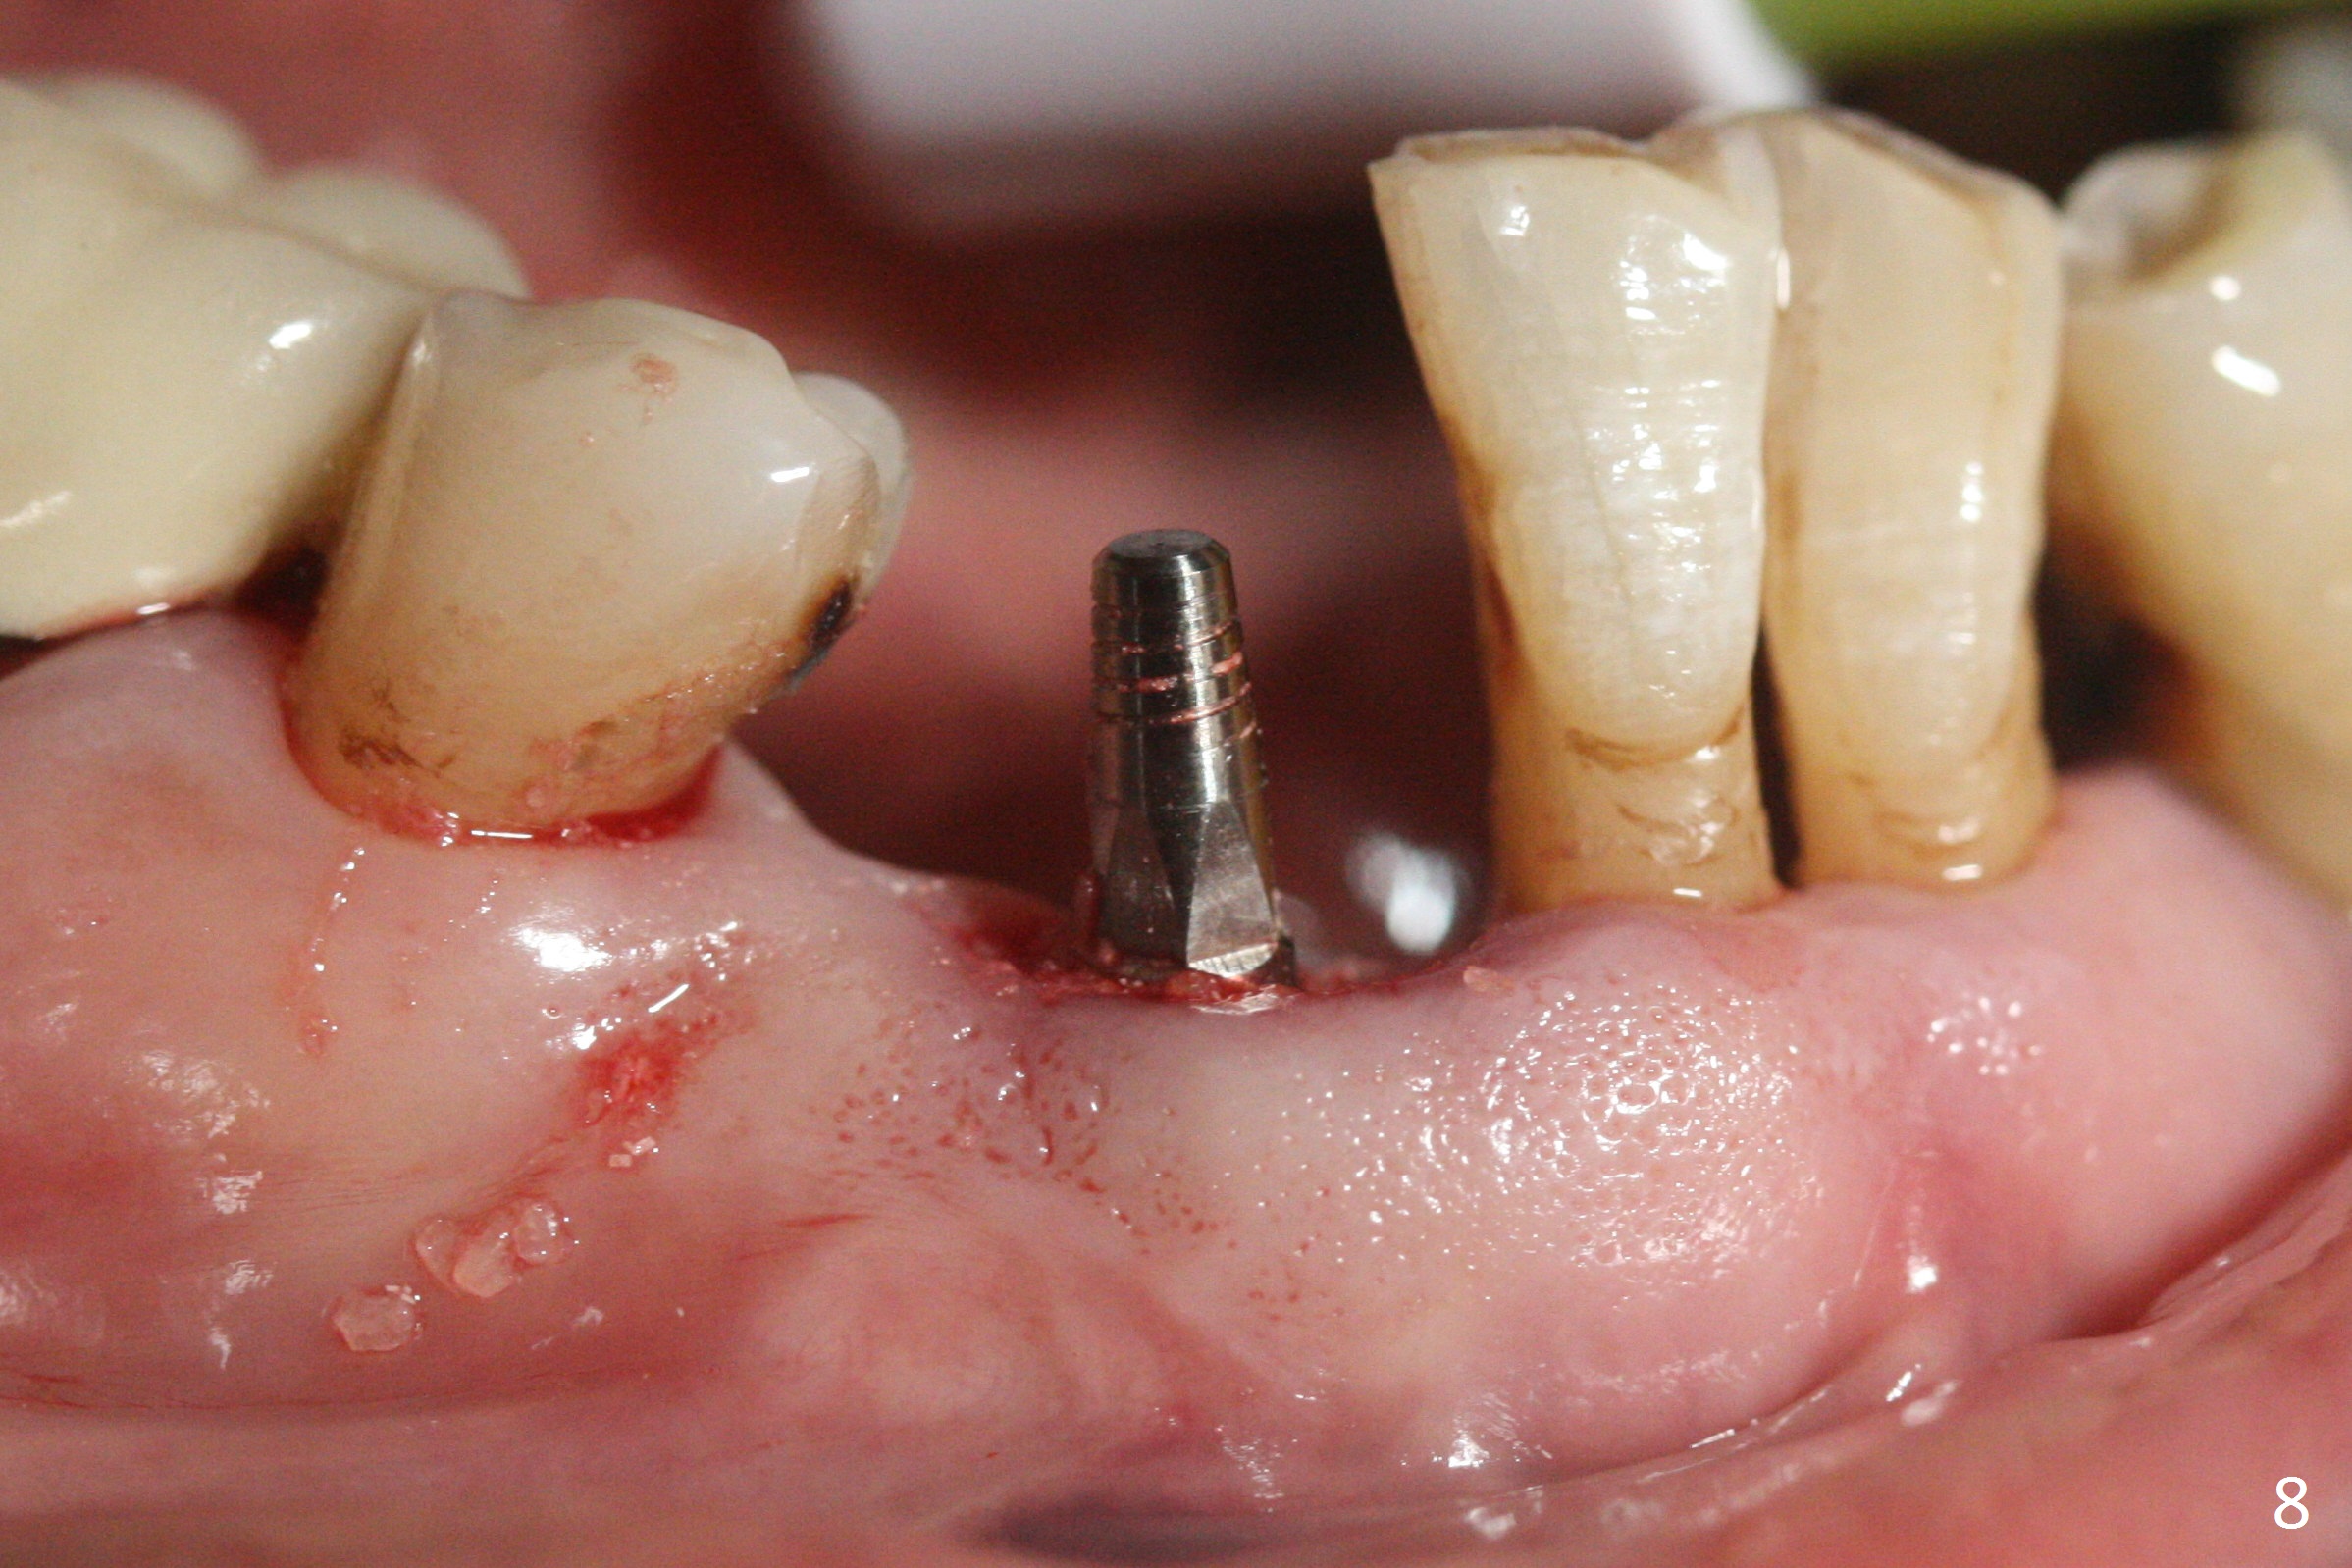

The lower dentition is special, consisting of a residual root (Fig.1 ^), 2 incisor (I), 1 canine (C), 1 premolar (P) and 1 molar (M). The residual root looks like an incisor with rotation of 90º (Fig.2,3). Osteotomy is initiated (Fig.4) for a 3x16(2) mm 1-piece implant (Fig.5 with 45 Ncm). The implant is being placed as distal as possible (Fig.4 arrow) so that a large canine-like provisional is to be fabricated in the large edentulous space (Fig.8,9) after bone graft (Fig.6,7 *). The gingiva around the provisional (Fig.10 P) remains healthy 11 days postop with occlusal clearance against the opposing dentition (Fig.11). The implant threads are not exposed with the help of bone graft 3 months 1 week postop (Fig.12). The gingiva around the implant is healthy (Fig.13). Soft tissue socket is formed by the provisional (Fig.14 *).